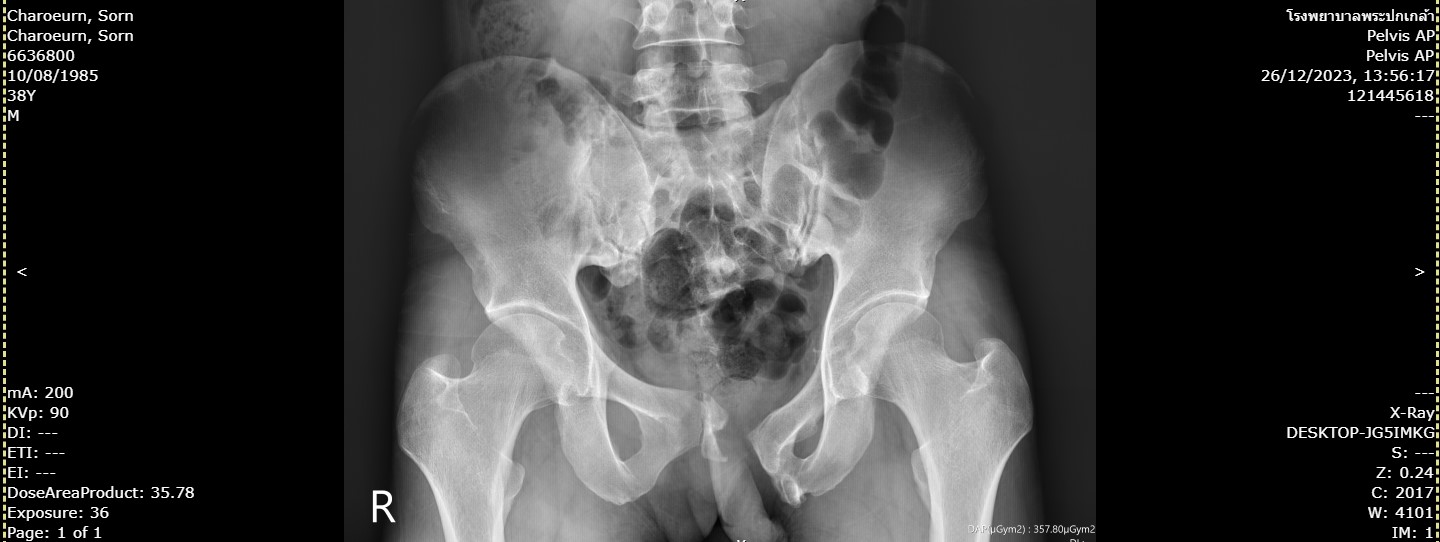

166charoeum.jpg                                    21-Apr-2024 09:02              113280